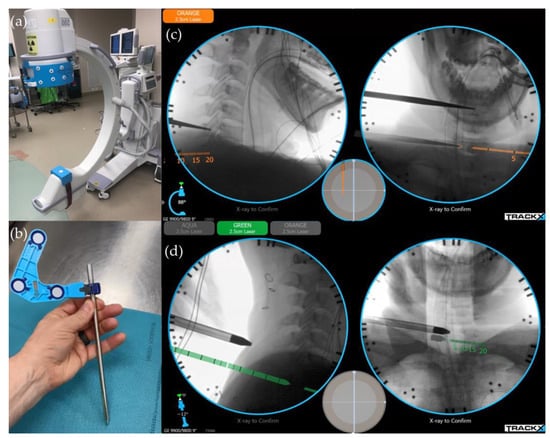

6.1. Image-Guided Navigation System/Instrument Tracking System